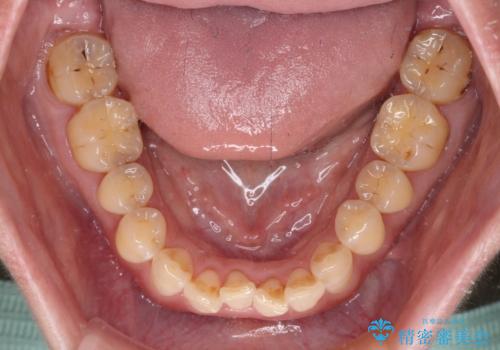

- 飛び出た上の前歯を気にして来院された患者様です。

奥歯の咬み合わせは、上顎歯列が理想的な一よりも数mm前方にある状態でした。

なるべく早めに治療を終えたいとのことで、補助装置を用いて上顎臼歯を後方に移動させ、同時にワイヤー装置にて整えることとしました。

舌の突出癖が原因で上下の歯に大きなスペースが生じていたため、舌のトレーニングをしっかり行っていただくことで、上顎歯列をスムーズに移動させることができました。